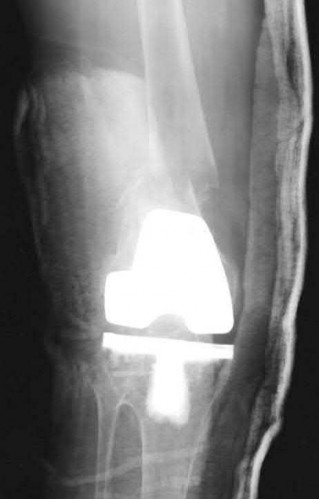

A 65-year-old man presents with anterior knee pain and a feeling of instability during stair climbing 1 year after a primary total knee arthroplasty.

Examination reveals a lateral patellar tilt. CT scan is performed to evaluate component rotation. Which of the following errors in component positioning is most likely responsible for his symptoms?

Explanation

Internal rotation of the femoral component or the tibial component increases the Q angle, leading to lateral patellar maltracking, lateral patellar tilt, and anterior knee pain. External rotation of the components generally improves patellar tracking.